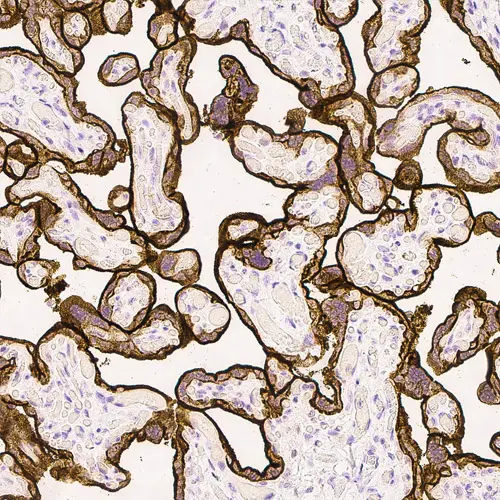

Human placenta: immunohistochemical staining for Epidermal Growth Factor Receptor. High expression of EGFR localized in the trophoblastic layer of the placental villi. Epidermal Growth Factor Receptor: clone EGFR.113

Antigen Background Epidermal Growth Factor Receptor (EGFR) is a transmembrane protein receptor of 170 kD with tyrosine kinase activity. Increased levels of EGFR are reported to be linked with malignant transformation of squamous cells e.g., in squamous cell carcinoma of the lung, head, neck, skin, cervix and esophagus. EGFR may also play a role in the development and progression of hepatocellular carcinomas where recurrence rates are higher in EGFR-positive cases. This correlation has similarly been reported in colorectal cancers where EGFR, produced by tumor cells, plays an important role in the invasiveness and proliferation of colorectal cancers. The majority of published studies of EGFR expression in human breast cancer has similarly shown an association with EGFR expression where it is inversely related to estrogen receptor status.

Product Specific Information Clone EGFR.113 is raised to the extracellular domain of the EGFR molecule.